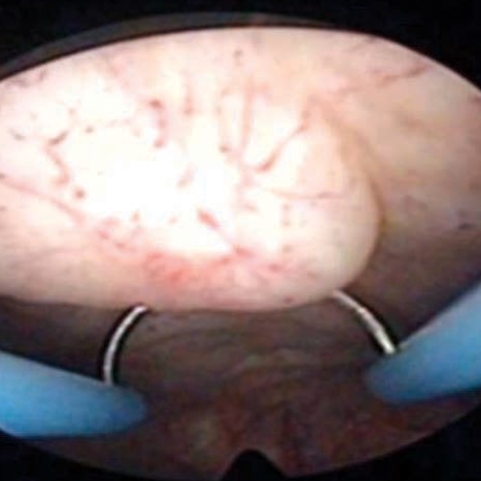

At operation, multiple spargana were found within the mass, around the spermatic cord and scrotal soft tissues (Figs. 1, 2). All identified spargana worms were completely excised. Diagnostic cystoscopy was performed consecutively to evaluate the microscopic hematuria, and a 10-mm sized small nodular mucosal elevation was found in the right side of the dome of the urinary bladder (Fig. 3). Covered mucosa was removed using resectoscope, and a whitish worm-like mass surrounded by granulation tissues was found inside of the nodule (Fig. 4). We tried to remove it by forceps, but it came apart. Histological examinations revealed a foreign body granuloma with a few infiltrates of eosinophils. In a serological test, patient's serum showed a positive reaction to anti-sparganum IgG antibody.